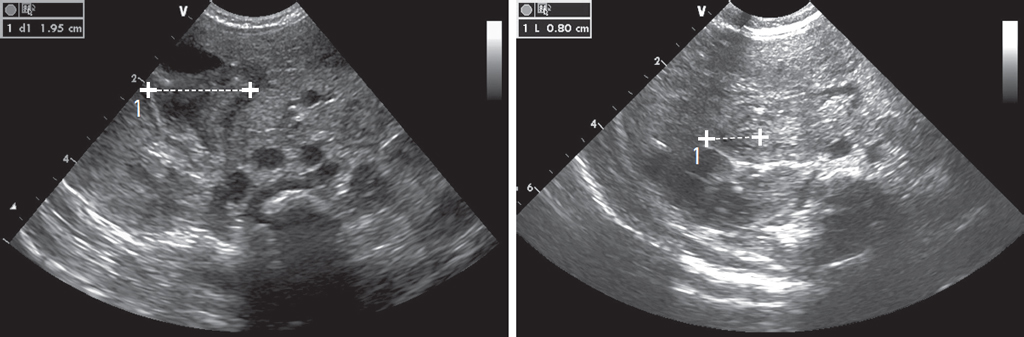

Одна из операций проведена на предмет высокой кишечной непроходимости, на УЗИ визуализировалась дилатированная двенадцатиперстная кишка — было высказано предположение о ее атрезии (рис. 7). Операция прошла без предварительного рентгенологического дообследования. При ревизии купол слепой кишки оказался высоко фиксирован эмбриональными тяжами к двенадцатиперстной кишке, тонкая и толстая кишка имели общую брыжейку, кишка спавшаяся, брыжейка перекручена на 180о. Тупо и остро разделены эмбриональные тяжи. При выделении от тяжей двенадцатиперстной кишки выявлена кольцевидная поджелудочная железа, фиксировавшая и сужавшая просвет кишки.

Рис. 7. Пример расширения двенадцатиперстной кишки у новорожденного на УЗИ, В-режим (слева). Второй сегмент двенадцатиперстной кишки у здорового новорожденного (справа)

Fig. 7. Example of duodenal dilatation in a newborn on ultrasound, B-mode (left). Second segment of the duodenum in a healthy newborn (right)

Визуализация третьего сегмента двенадцатиперстной кишки линейным датчиком 10–12 МГц в норме возможна всегда при достаточном опыте работы. Врачи не описывали третий сегмент в протоколе в большинстве случаев, если визуализировали его на месте и не было атипичного расположения сосудов брыжейки. Если сосуды расположены атипично, то третьего сегмента практически никогда нет в аорто-мезентериальном пространстве, поэтому врачи также не указывают его в заключении. Только если третий сегмент визуализируется на месте при атипичном взаиморасположении сосудов, это отмечается в протоколе, так как не является логичным.